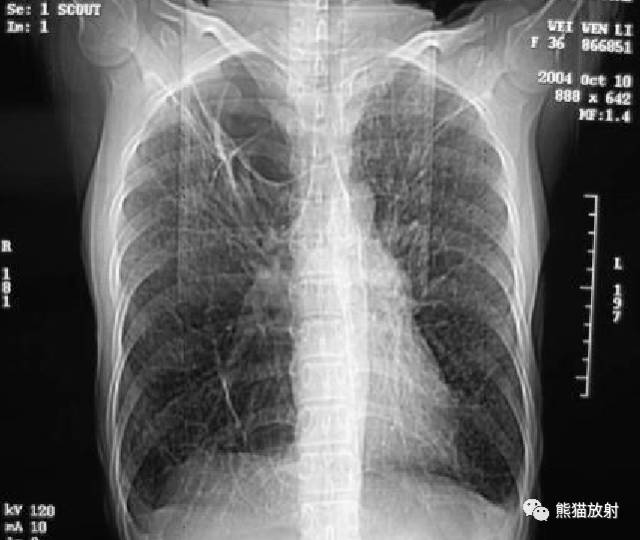

女,36岁,胸闷,胸疼,气短一个月,以往有肺大泡切除史。

【影像表现】

胸部CT:双肺弥漫分布大小不等薄壁囊状空气密度影,且胸膜下区低密度影明显较其他部位大,周围见索条状高密度影。阴影之间肺组织基本正常。